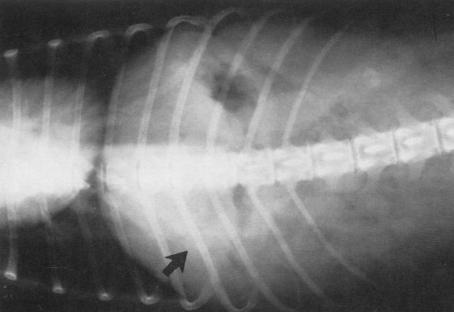

X光线可见结石大小(箭头位置)

实验室检查X光线能检查肝脏区域胆囊位置是否有结石,但必须配合超声检查,这样结果来得更清晰,因有时候胆囊结石会与胆管结石同时存在。超声检查可以检测胆囊直径> 2 mm的结石

胆囊结石可以说经常出现在中老年犬身上,但临床上发生的案例不多,检查时必须以X光线和超声波检查作为标配去检查胆囊区域的影像。